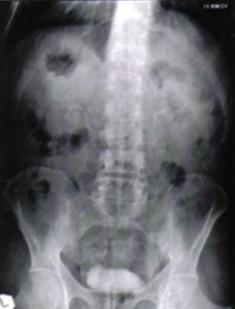

a) Radiografie renovezicala simpla (RRVS) si urografie intravenoasa (UIV)

Fig.8 Imagini lacunare in aria vezicii urinare sugerand tumori vezicale superficiale [51].